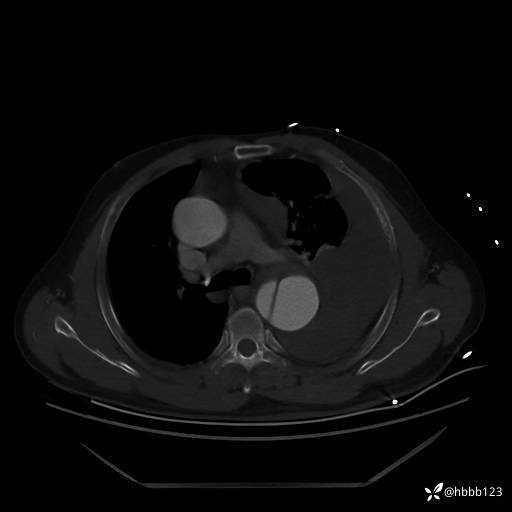

急查胸腹主动脉CTA:

(为方便观察,调至骨窗)